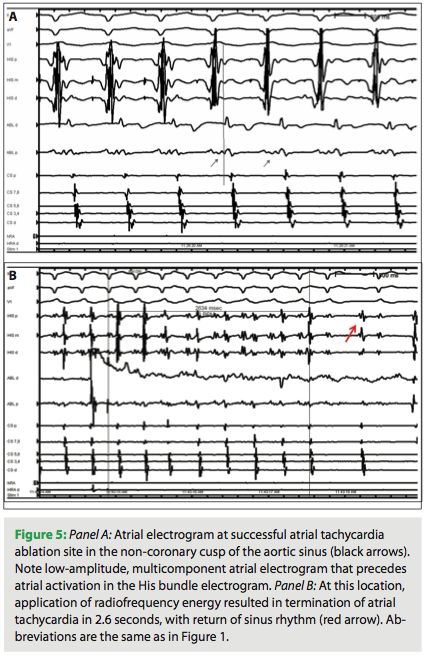

The ablation catheter was advanced to the aortic root under fluoroscopic and intracardiac echo guidance (Figure 4, Panels A and B). At this location, low amplitude, multicomponent atrial electrograms with activation times earlier than those in the His bundle region were noted (Figure 5, Panel A). Ablation at this location terminated SVT in 2.6 sec (Figure 5, Panel B). Ablation catheter location at the successful site in NCC is shown in Figure 6 (Panels A and B). Two 60-second applications were delivered at this location (30 W, 55° C), and AT was no longer inducible despite aggressive testing. Patient remained arrhythmia-free at one-month follow up. There were no complications.